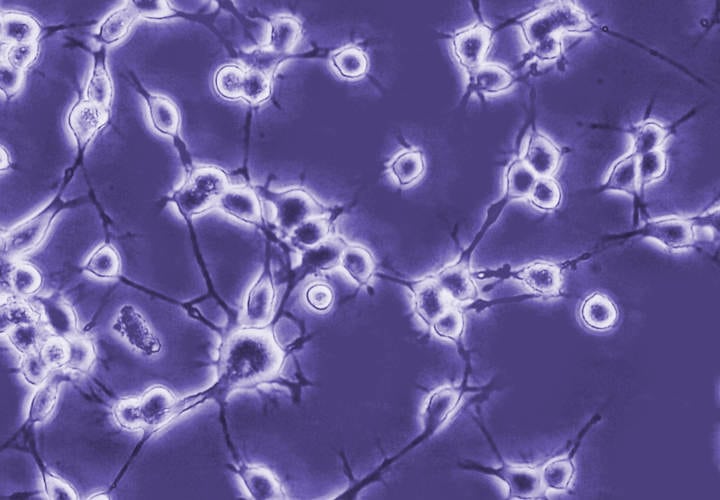

• La utilización de transplantes celulares se encuentra todavía en fase de experimentación en modelos animales.